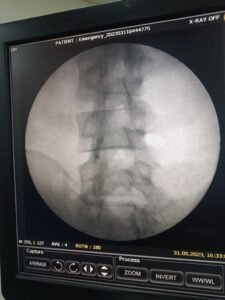

Once the PRP is prepared, it is injected directly into the affected facet joints under guided imaging, such as fluoroscopy or ultrasound, to ensure precise targeting. The growth factors and proteins present in PRP help reduce inflammation, promote tissue regeneration, and stimulate the production of new cells and collagen. The treatment process is minimally invasive, usually completed as an outpatient procedure, and requires minimal recovery time.